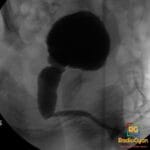

- Radiology Cases: Images with a to-the-point discussion highlighting the specific diagnostic criteria.

Latest Radiology Cases